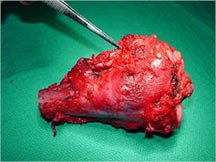

- Telangiectatic osteosarcomas have a variable gross appearance

- They may appear as a large blood clot filling a single large cystic cavity; hemorrhagic and necrotic mass; or a multicystic fluid-filled lesion

- Thin septae exist between the cystic cavities that harbor malignant appearing spindle cells producing scant osteoid

- Fleshy and sclerotic tissue typical of a conventional osteosarcoma is not seen

- Its gross appearance can mimic an aneurysmal bone cyst

- Mixture of large cystic and spongy areas